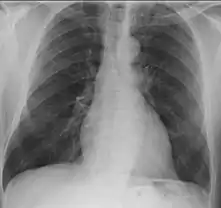

- Lungs: abnormal chest X-ray with:

- nodules,

- infiltrates or

- cavities